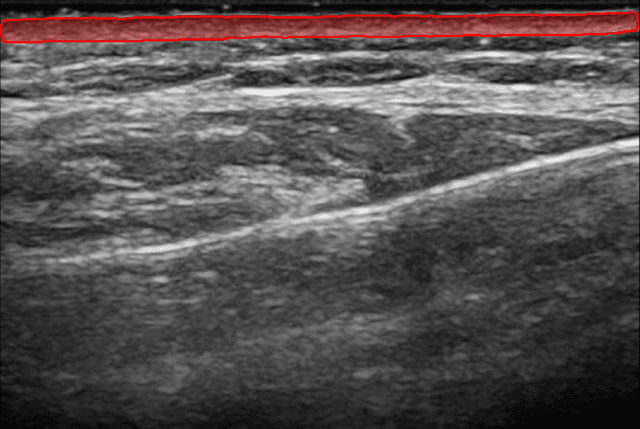

Nuestra IA segmenta instantáneamente tu capa dérmica. Obtén mediciones precisas de el grosor y el área de la dermis.

Sigue mejoras medibles a lo largo de las sesiones de tratamiento. Visualiza cambios en la calidad de la dermis con comparaciones precisas de antes y después.